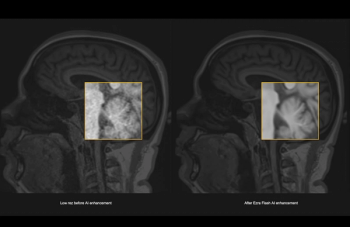

The artificial intelligence (AI)-powered Ezra Flash reportedly enhances magnetic resonance imaging (MRI) and enables significant reductions in scan times and costs for full-body MRI.